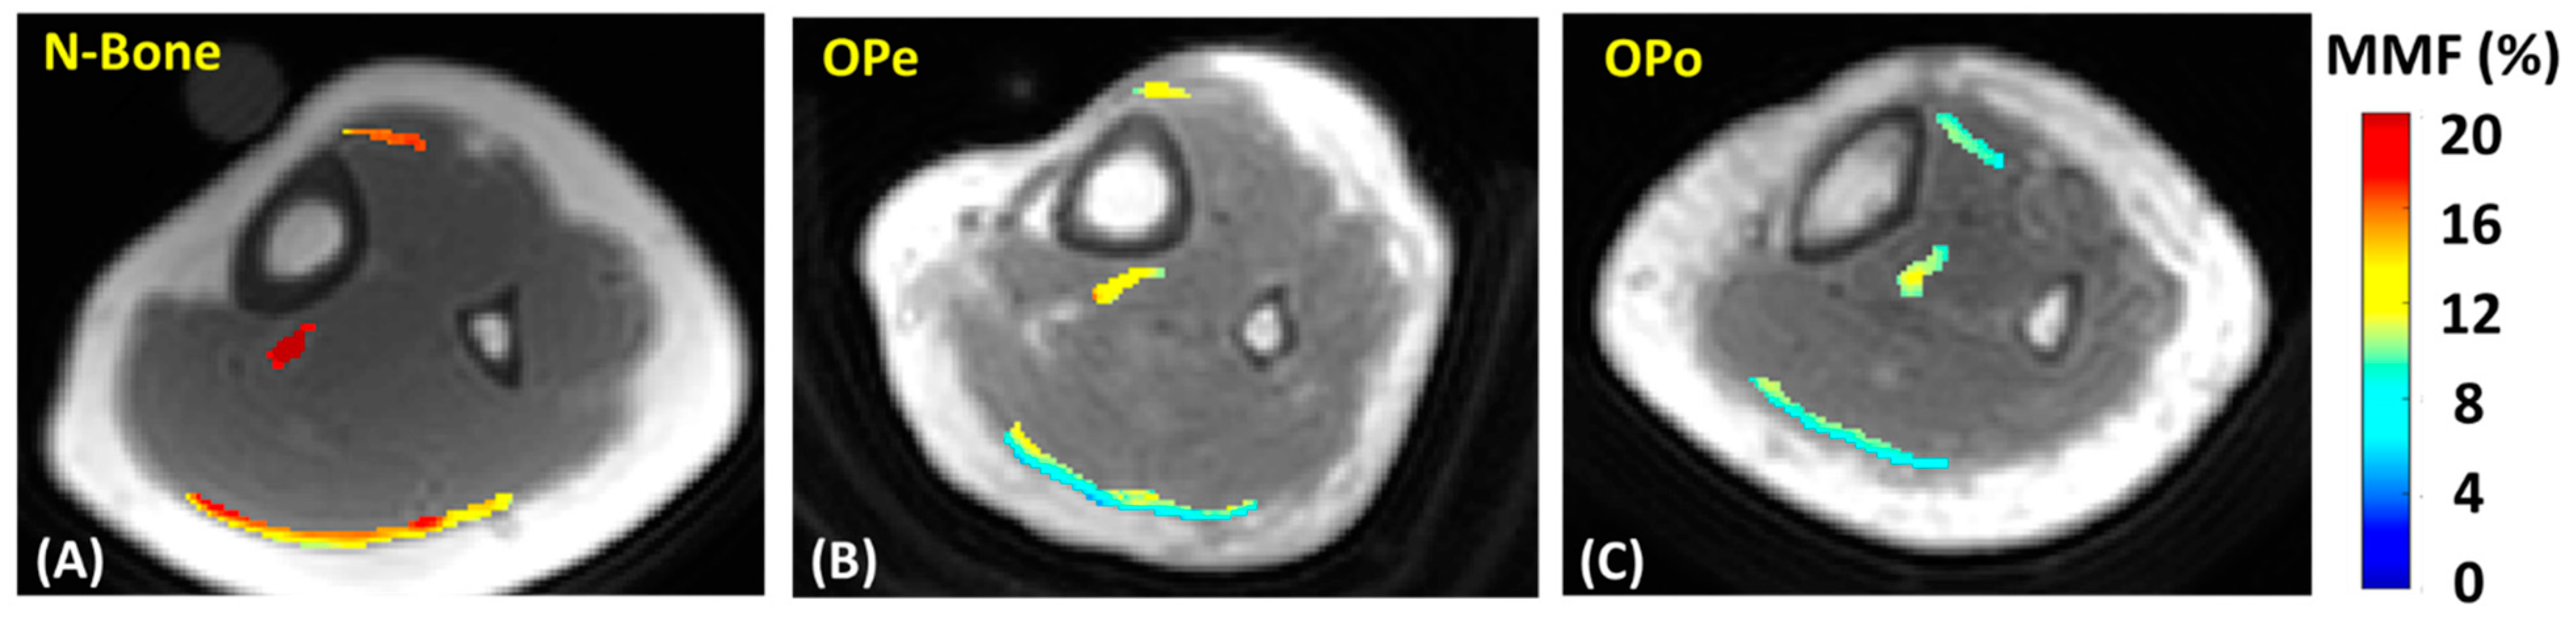

Figure 2 shows MMF maps generated for the tendons of three exemplary participants from the Normal-Bone, OPe, and OPo cohorts. For these examples, MMF values were observed in the following ascending order: OPo < OPe < Normal-Bone.

Generated macromolecular proton fraction (MMF) maps for exemplary participants from (A) Normal-Bone cohort (23-year-old female), (B) OPe cohort (83-year-old female), and (C) OPo cohort (85-year-old female). MMF was higher in Normal-Bone participant compared with OPe and OPo patients. N-Bone label refers to Normal-Bone group.